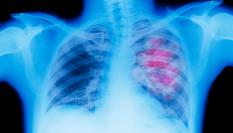

Los resultados de este ensayo clínico “no tienen precedentes”. Un artículo publicado el 5 de junio en el New England Journal of Medicine describe un ensayo clínico realizado en 12 pacientes con cáncer colorrectal. Durante seis meses, estos pacientes recibieron una dosis de dostarlimab cada tres semanas. Con este tratamiento, quedaron completamente curados.

El dostarlimab, el medicamento administrado a los pacientes del ensayo clínico, es un tratamiento de inmunoterapia, es decir, “un tratamiento dirigido al sistema inmunitario”. Son tratamientos relativamente nuevos: están en prueba desde 2013 en Estados Unidos.

“En muchos tipos de cáncer, las células cancerosas neutralizan las células inmunitarias para que que no puedan atacarlas”, explica la profesora Moyret-Lalle. Las inmunoterapias, combinadas con la quimioterapia, permiten que las células inmunitarias vuelvan a atacar a las células tumorales.

Sin embargo, no son tratamientos eficaces en todos los tipos de cáncer colorrectal. En el caso de este ensayo clínico, la prueba se realizó en un tipo concreto de cáncer colorrectal, que representa, como máximo, el 20% de los casos.

“Se trata de cánceres colorrectales que presentan una inestabilidad genética particular llamada inestabilidad de microsatélites”, explica la investigadora. “No es el caso del 80 al 90% de los cánceres colorrectales, es decir, la gran mayoría”.